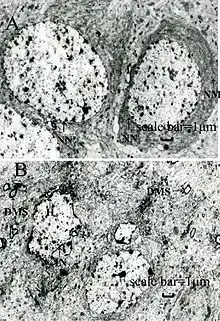

Blood film examination may reveal basophilic stippling of red blood cells (dots in red blood cells visible through a microscope), as well as the changes normally associated with iron-deficiency anemia (microcytosis and hypochromasia).[64] This may be known as sideroblastic anemia.[204] However, basophilic stippling is also seen in unrelated conditions, such as megaloblastic anemia caused by vitamin B12 (colbalamin) and folate deficiencies.[205] Contrary to other sideroblastic anemia, there are no ring sideroblasts in a bone marrow smear.[206]

Exposure to lead also can be evaluated by measuring erythrocyte protoporphyrin (EP) in blood samples.[34] EP is a part of red blood cells known to increase when the amount of lead in the blood is high, with a delay of a few weeks.[28] Thus EP levels in conjunction with blood lead levels can suggest the time period of exposure; if blood lead levels are high but EP is still normal, this finding suggests exposure was recent.[28][37] However, the EP level alone is not sensitive enough to identify elevated blood lead levels below about 35 μg/dL.[34] Due to this higher threshold for detection and the fact that EP levels also increase in iron deficiency, use of this method for detecting lead exposure has decreased.[207]

Blood lead levels are an indicator mainly of recent or current lead exposure, not of total body burden.[208] Lead in bones can be measured noninvasively by X-ray fluorescence; this may be the best measure of cumulative exposure and total body burden.[37] However, this method is not widely available and is mainly used for research rather than routine diagnosis.[103] Another radiographic sign of elevated lead levels is the presence of radiodense lines called lead lines at the metaphysis in the long bones of growing children, especially around the knees.[209] These lead lines, caused by increased calcification due to disrupted metabolism in the growing bones, become wider as the duration of lead exposure increases.[209] X-rays may also reveal lead-containing foreign materials such as paint chips in the gastrointestinal tract.[26][209]